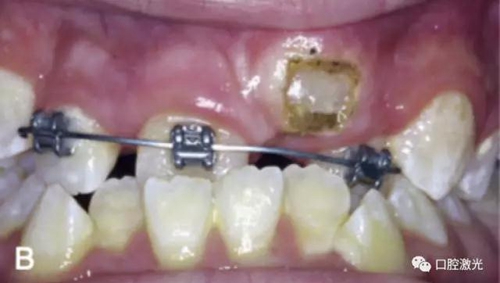

治療前

激光牙齦切割后即刻

在近似理想位置粘接托槽

6周后效果